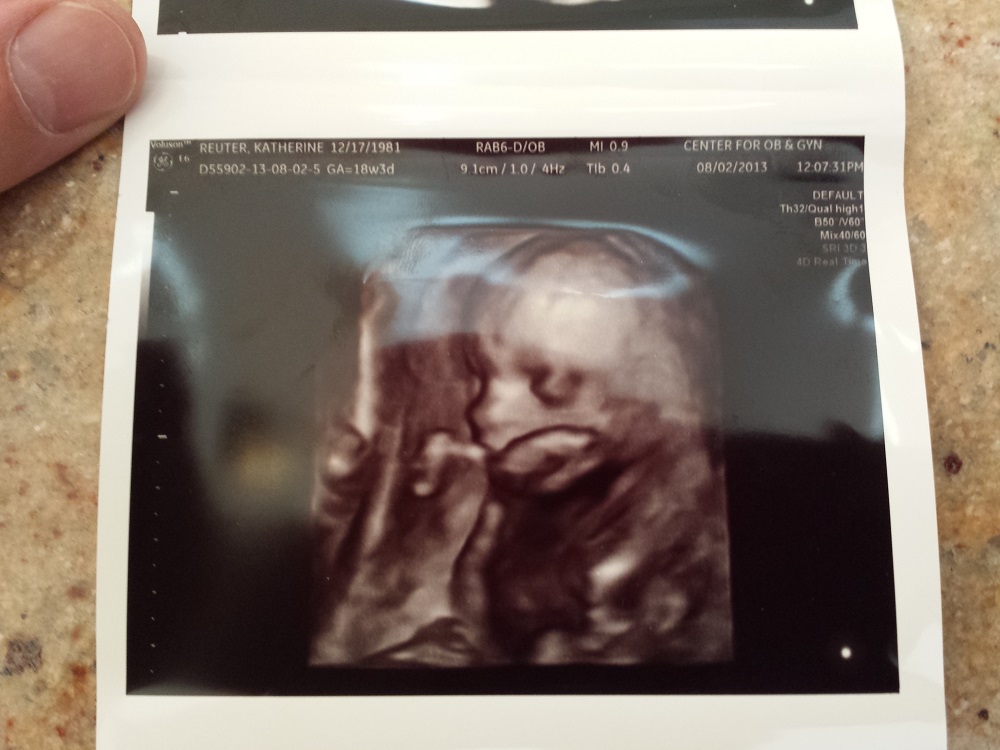

I promise this is the last thread I am posting then my OCD with this will stop hehe You guys are awesome for helping! Since I don't have any good nub shots can you take a look at the shape of the skull and make your best guess! xo

Attachment 12862